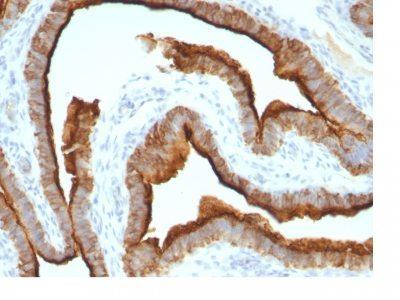

MCF-7 or MDA-231 cells. Breast, colon, ovarian, endometrial carcinoma.

Immunohistology formalin-paraffin 0.25-0.5 ug/mL|Staining of formalin-fixed tissues requires boiling tissue sections in 10 mM citrate buffer, pH 6.0, for 10-20 min followed by cooling at RT for 20 minutes|Flow Cytometry 0.5-1 ug/million cells/0.1 mL|Immunofluorescence 1-2 ug/mL|Optimal dilution for a specific application should be determined by user